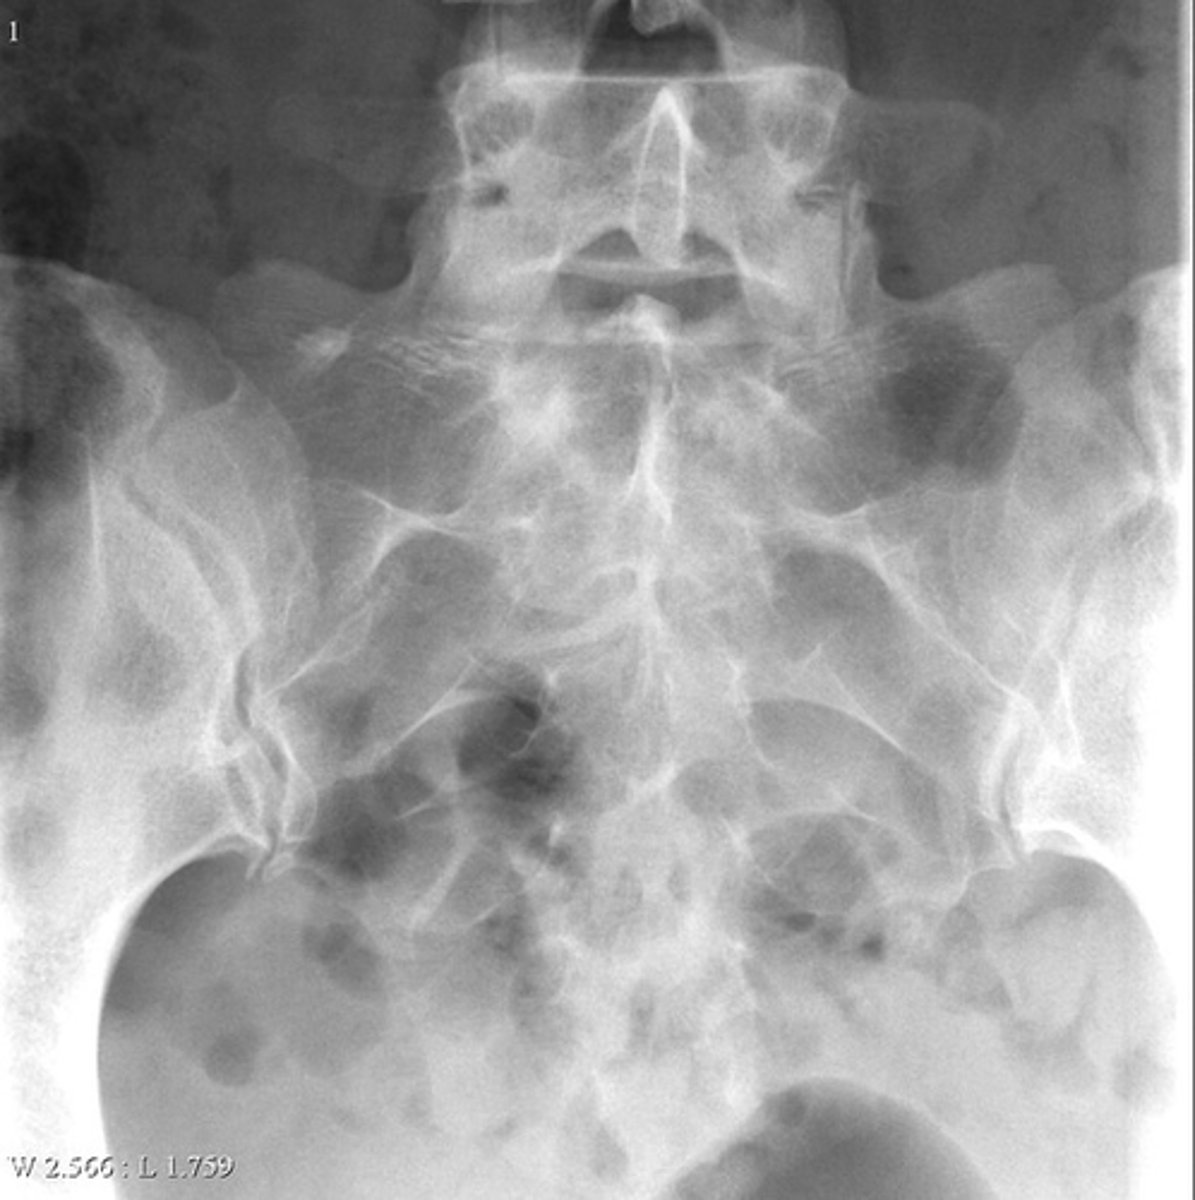

- Superior aspect of sacrum on right side

- Lucent/opaque brush-border oval

Describe the lesion

<p>Describe the lesion</p>

Bone island

Most likely diagnosis?

<p>Most likely diagnosis?</p>

Nothing

Next step?

<p>Next step?</p>